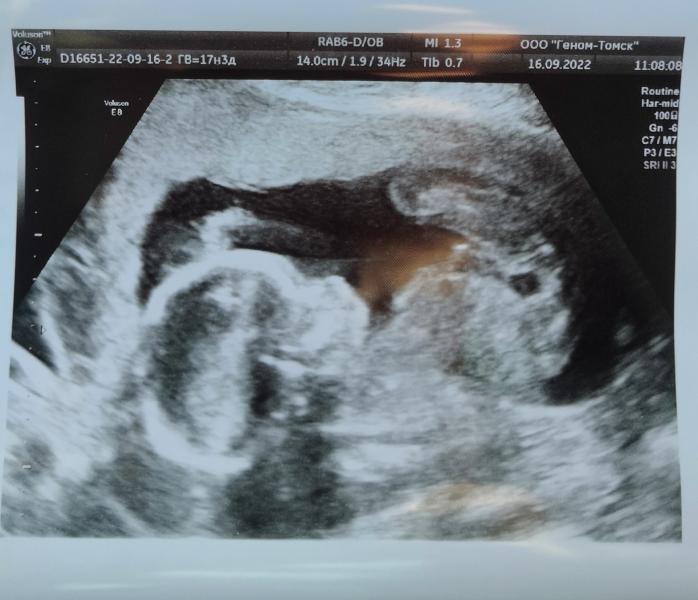

У нас мальчик! 👨👩👦

У нас абсолютно не было ожиданий на счёт пола, кто есть, тот есть, это предопределено с первой секунды зачатия). Но было приятно именно узнать, теперь понятней, как обращаться к ребёнку, теперь можно придумывать имя и покупать вещички)).

Я всегда счастлива в день УЗИ, он там так классно шевелится 🥰.